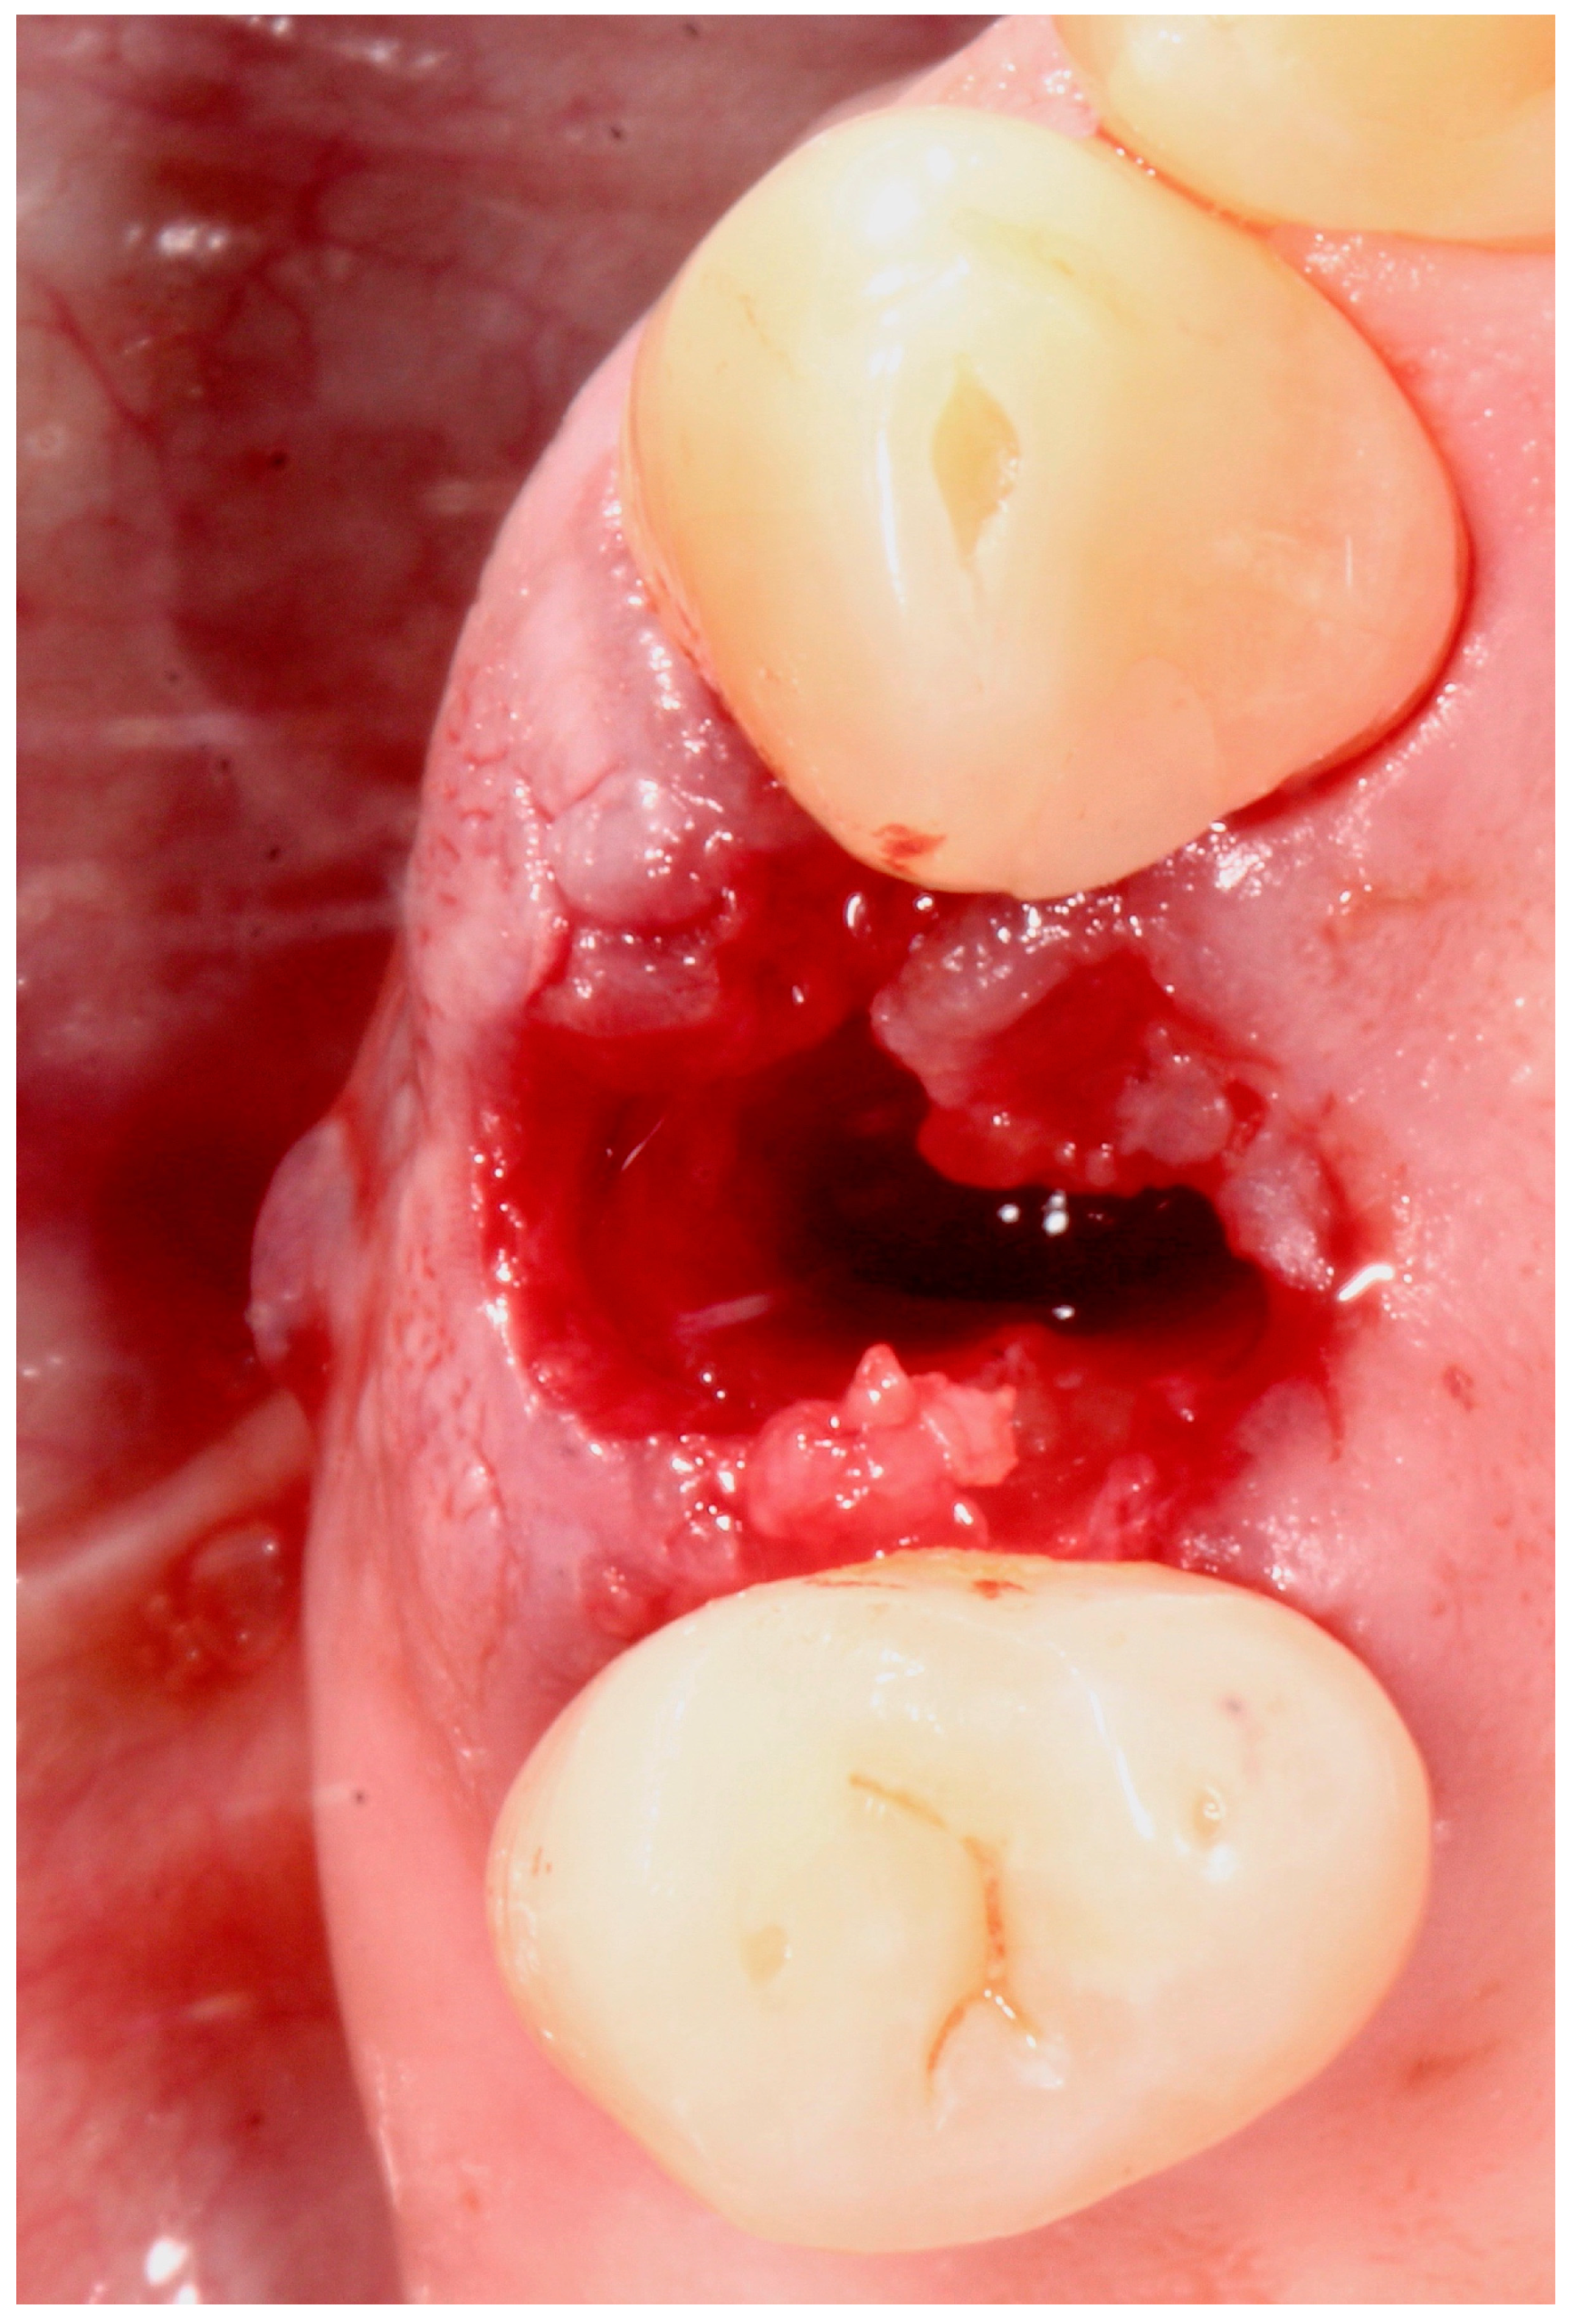

5.4. Surgical Technique